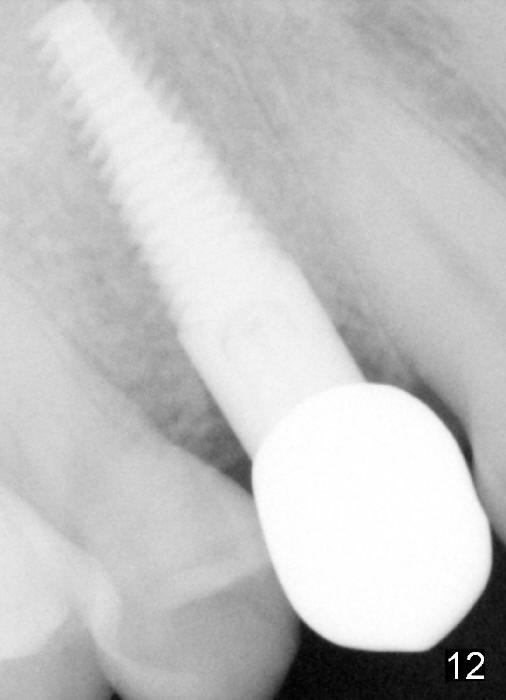

The patient returns 6 months postop for impression of a permanent restoration. The gingiva with knife-edged papillae adapts to the provisional (Fig.7). The gingiva looks healthy when the provisional is removed (Fig.8). The buccal bone resorption seems to be minimal, as compared to Fig.1,2. There is no bone loss between immediately postop (Fig.9 I; implant), 4.5 months postop (Fig.10 A: abutment), 4 and 7 months post cementation (Fig.11,12 C: crown). Soft and hard tissue morphology remains normal 7 months post cementation (Fig.13). No bone loss is observed 15 months post cementation (Fig.14). The papillae (Fig.15) and bone (Fig.16,17) remain stable 29 months post cementation.

The long implant seems to be appropriate for the patient with periodontitis and bruxism (Fig.18, 2 years, 10 months post cementation). The implant appears to be placed buccally (B, Fig.19,20 (CBCT coronal and axial sections), 4 years, 5 months post cementation).